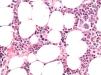

With these findings and due to the severity of the clinical situation, empirical treatment with HLH-94 protocol6 was started. Liver and renal dysfunction corrected, cytopenias improved, coagulation tests normalized, fever disappeared and ferritin levels decreased after 2 weeks of treatment and sIL-2r decreased to 1350 U/ml. After 3 weeks on treatment, fever reappeared, anemia (Hemoglobin 7,8 gr/dl) and ferritin of 3076 ng/mL were observed. At this point bone marrow biopsy was informed which showed infiltration by Intravascular Large B cell Lymphoma with no evidence of hemophagocytosis (Figures 1 and 2).